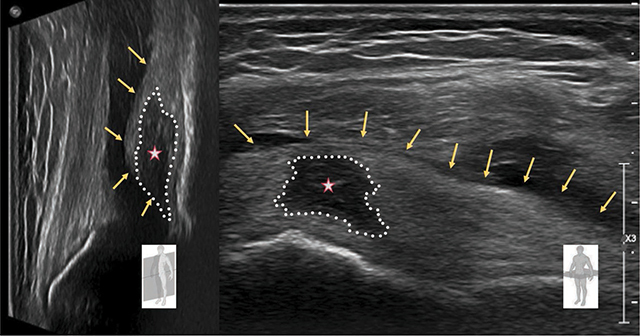

教学要点:股骨前脂肪垫撞击综合征是膝关节脂肪垫撞击的一种,可通过超声波检查进行评估。

Teaching point: Prefemoral fat pad impingement syndrome is one of the fat pad impingements of the knee and can be assessed with ultrasonography.